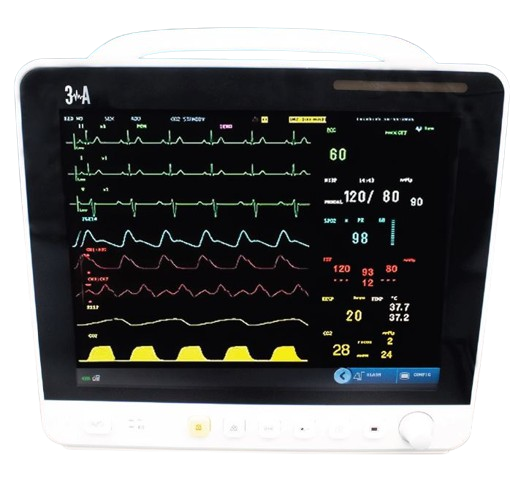

Patient Monitor - medexbio

Patient Monitor - medexbio

PATIENT MONITOR 5 PARMETERS

PATIENT MONITOR 5 PARMETERS

PATIENT MONITOR

PATIENT MONITOR

VITAL SIGN MONITOR

VITAL SIGN MONITOR

New E7 Portable Patient Monitor

New E7 Portable Patient Monitor

M10 vital signs monitor - Germany

M10 vital signs monitor - Germany

M20 vital signs monitor - GERMANY

M20 vital signs monitor - GERMANY

PROVIEW 10 PATENT MONITOR - GERMANY

PROVIEW 10 PATENT MONITOR - GERMANY

Patient Monitor for Adult Children Neonate

Patient Monitor for Adult Children Neonate

Vital Sign Monitor Aveus AV-Vital X

Vital Sign Monitor Aveus AV-Vital X

BISTOS BT-720 VITAL SIGN MONITOR

BISTOS BT-720 VITAL SIGN MONITOR

Dawei HM10 multi-parameter patient monitor

Dawei HM10 multi-parameter patient monitor

Superstarmed SP J12 multi-parameter patient monitor

Superstarmed SP J12 multi-parameter patient monitor

Philips IntelliVue X3 Multiparameter Monitor

Philips IntelliVue X3 Multiparameter Monitor

Comen – NC5 Vital Signs Monitor

Comen – NC5 Vital Signs Monitor

VITAL SIGN MONITOR

VITAL SIGN MONITOR

3A PATIENT MONITOR DUBAI

3A PATIENT MONITOR DUBAI

.png) Bistos BT-740 Patient Monitor

Bistos BT-740 Patient Monitor

Philips IntelliVue MX450 Patient monitor

Philips IntelliVue MX450 Patient monitor

Patient Monitor M8

Patient Monitor M8

CARDIAC MONITOR

CARDIAC MONITOR